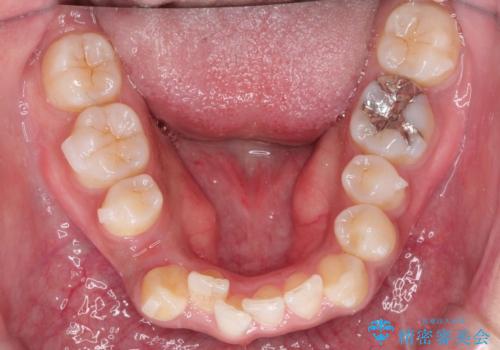

インビザラインと補助装置の併用による八重歯の抜歯矯正

- 八重歯を治したいとのことで来院されました。

重なりが強い右側の上下の歯を1本ずつ抜歯する計画としました。

インビザラインでの治療がご希望でしたが、右上の歯のかさなりが強いところは、補助装置である程度動かしてからインビザラインに移行することにしました。

下顎はインビザラインのみで治療を行いました。